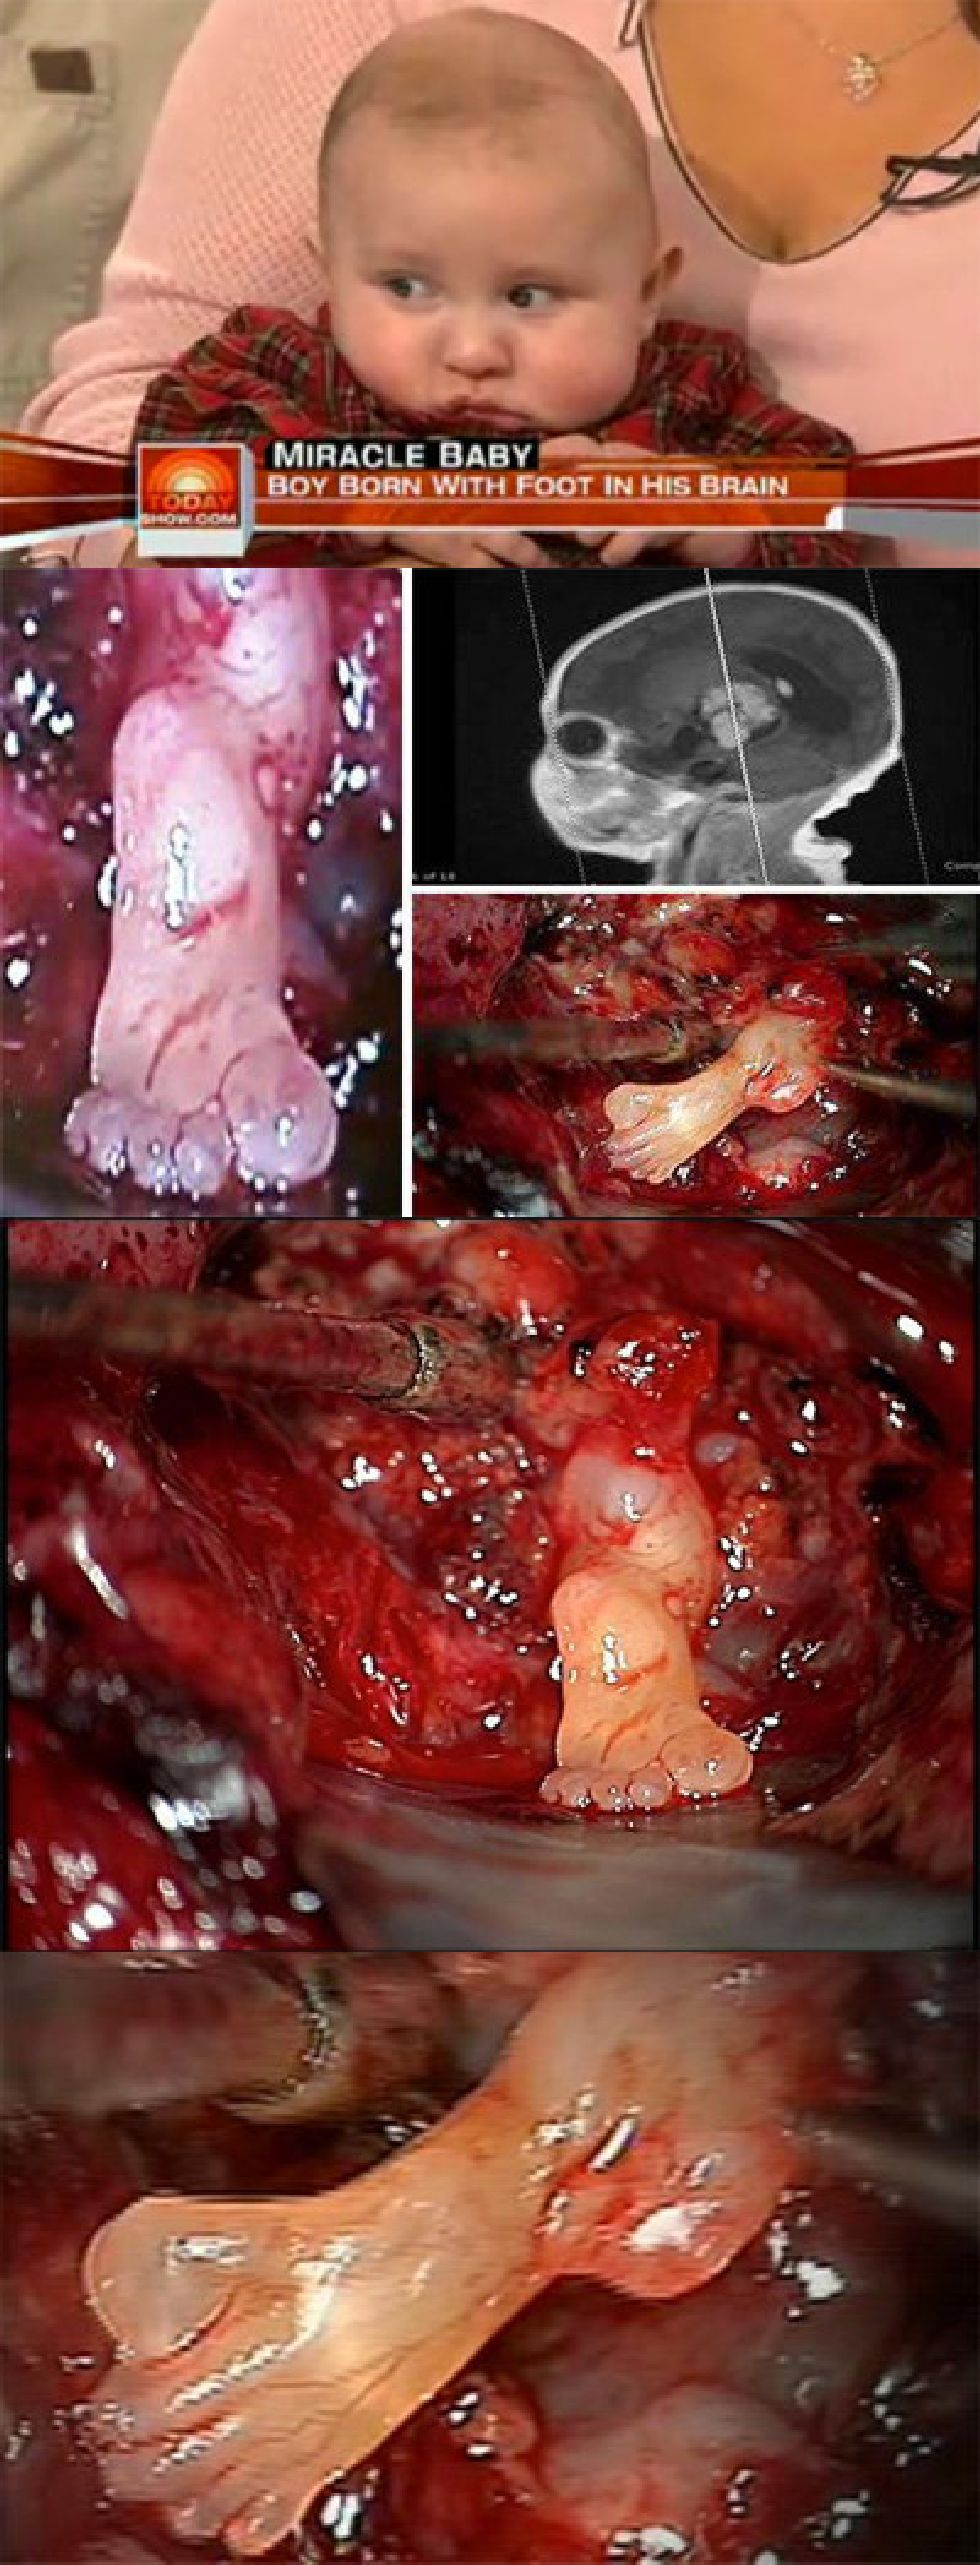

NSFWUn bébé né avec un pied dans le cerveau..

Malgré que ce soit un peu gore, je trouve cela intéressant.

Pour info il s\'agit d\'une tumeur, cela se produit lorsqu\'un f½tus entre en contact avec un autre f½tus jumeau. D\'ailleurs, dans le cerveau, le chirurgien a retrouvé une main, un autre pied et une cuisse en formation. En somme, le bébé avait son frère jumeau dans le cerveau....

Pareil, gore peux être, mais plus intéressant qu\'une bonne partie des trucs usless/pas drôle/inutile de choualbox, Voilà un fait divers unique et intéressant...

Une source parmi d\'autres: http://www.gentside.com/enfant/un-bebe-na-t-avec-un-pied-dans-la-tete_art3234.html